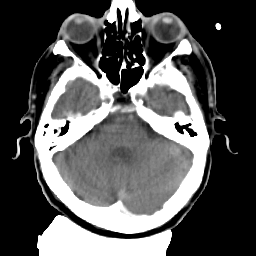

Meningioma: Roentgen-ray CT #2 -- Slice #5

[Home][Help][Clinical] Slice 5